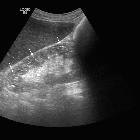

Ultrasound

Unique imaging appearance of numerous uniform microcysts and punctate echogenic foci which may be cortical or medullary in origin . The kidneys are normal in size.